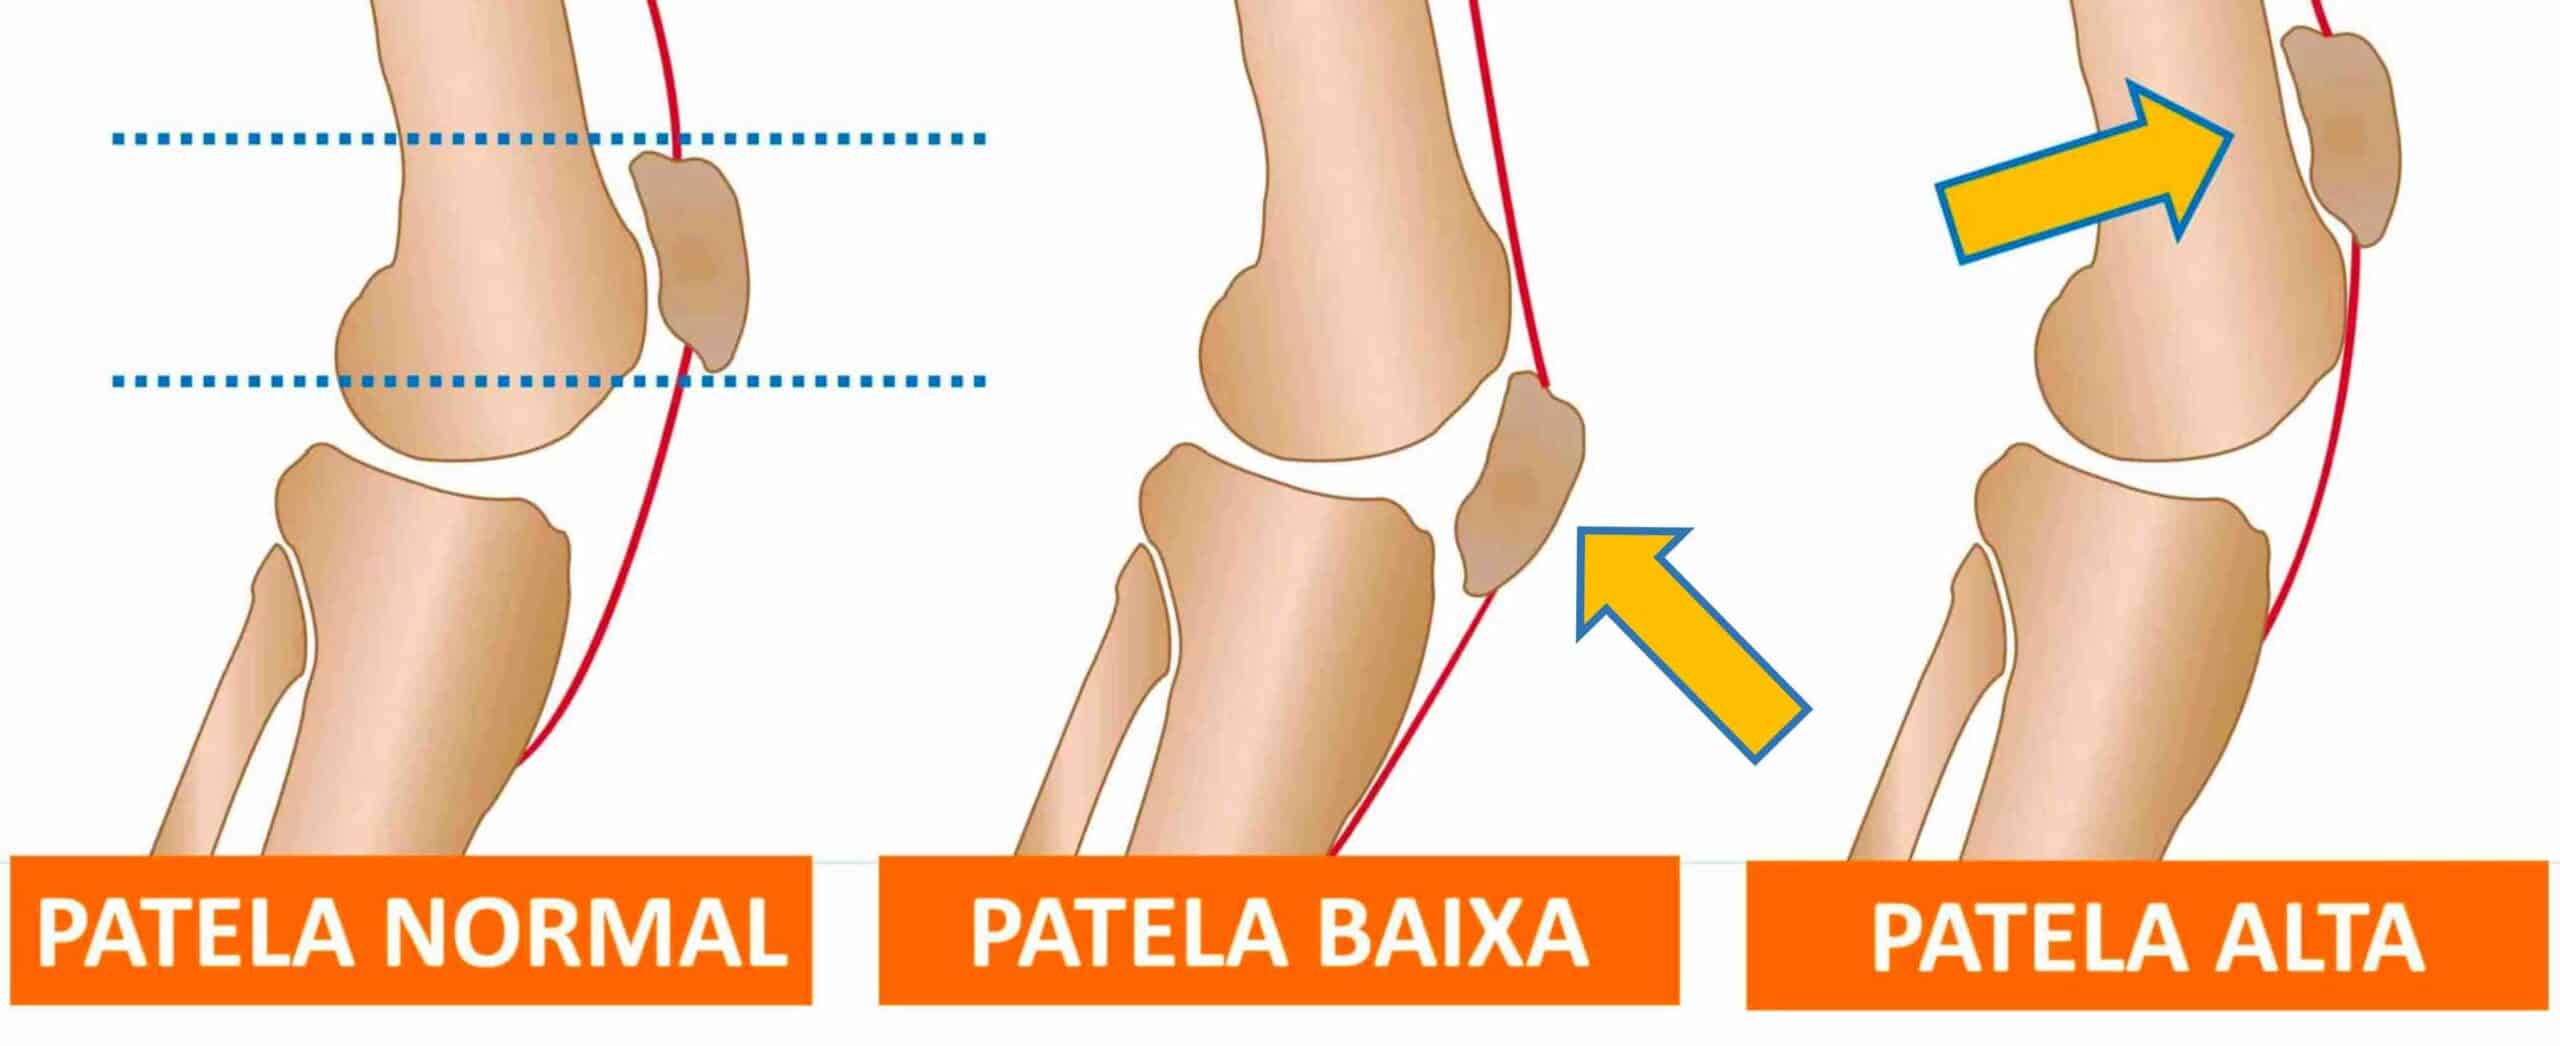

A patela é o osso móvel localizado na frente do joelho. Ela se articula com a tróclea femoral, que é um sulco côncavo localizado na região anterior do fêmur distal. A patela é o maior osso sesamóide do nosso corpo e está inserida dentro do tendão do músculo quadríceps femoral, fazendo parte do mecanismo extensor do joelho. A patela funciona como uma polia para o músculo quadríceps, aumentando a sua vantagem mecânica. Para que o joelho funcione com eficiência e sem dor, a patela deve estar perfeitamente alinhada na tróclea femoral. Quando a patela está localizada acima do normal, chamamos de patela alta. Quando a patela está localizada abaixo do normal, chamamos de patela baixa. A altura da patela é que determina se ela está numa altura normal, alta ou baixa em relação à tíbia. Patela alta é frequentemente associada a instabilidade patelar crônica, luxação patelar recidivante e condromalácia patelar. Já a patela baixa, ou patella infera, costuma estar associada a cirurgias ou traumatismos e pode causar limitação da amplitude de movimento, dor anterior intensa no joelho e degeneração precoce da cartilagem patelar.